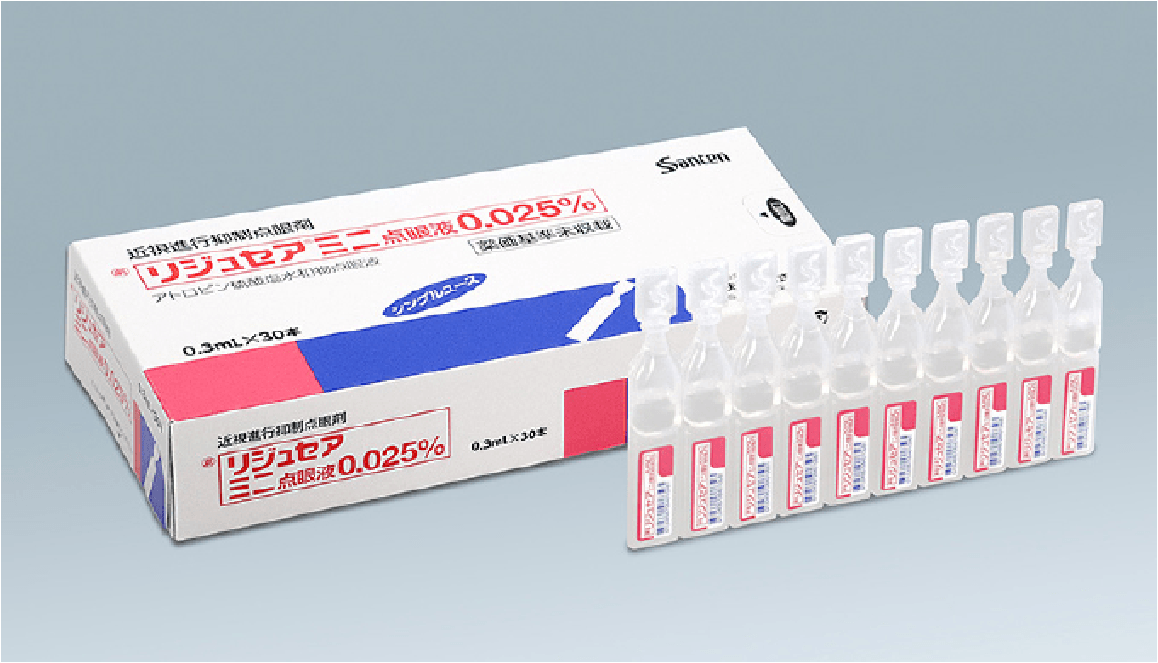

お子さまの将来の視力を守るために、近視進行抑制治療を行っています。

生活習慣へのアドバイスから点眼・コンタクト治療まで

一人ひとりに合わせた丁寧なサポートを行っています。